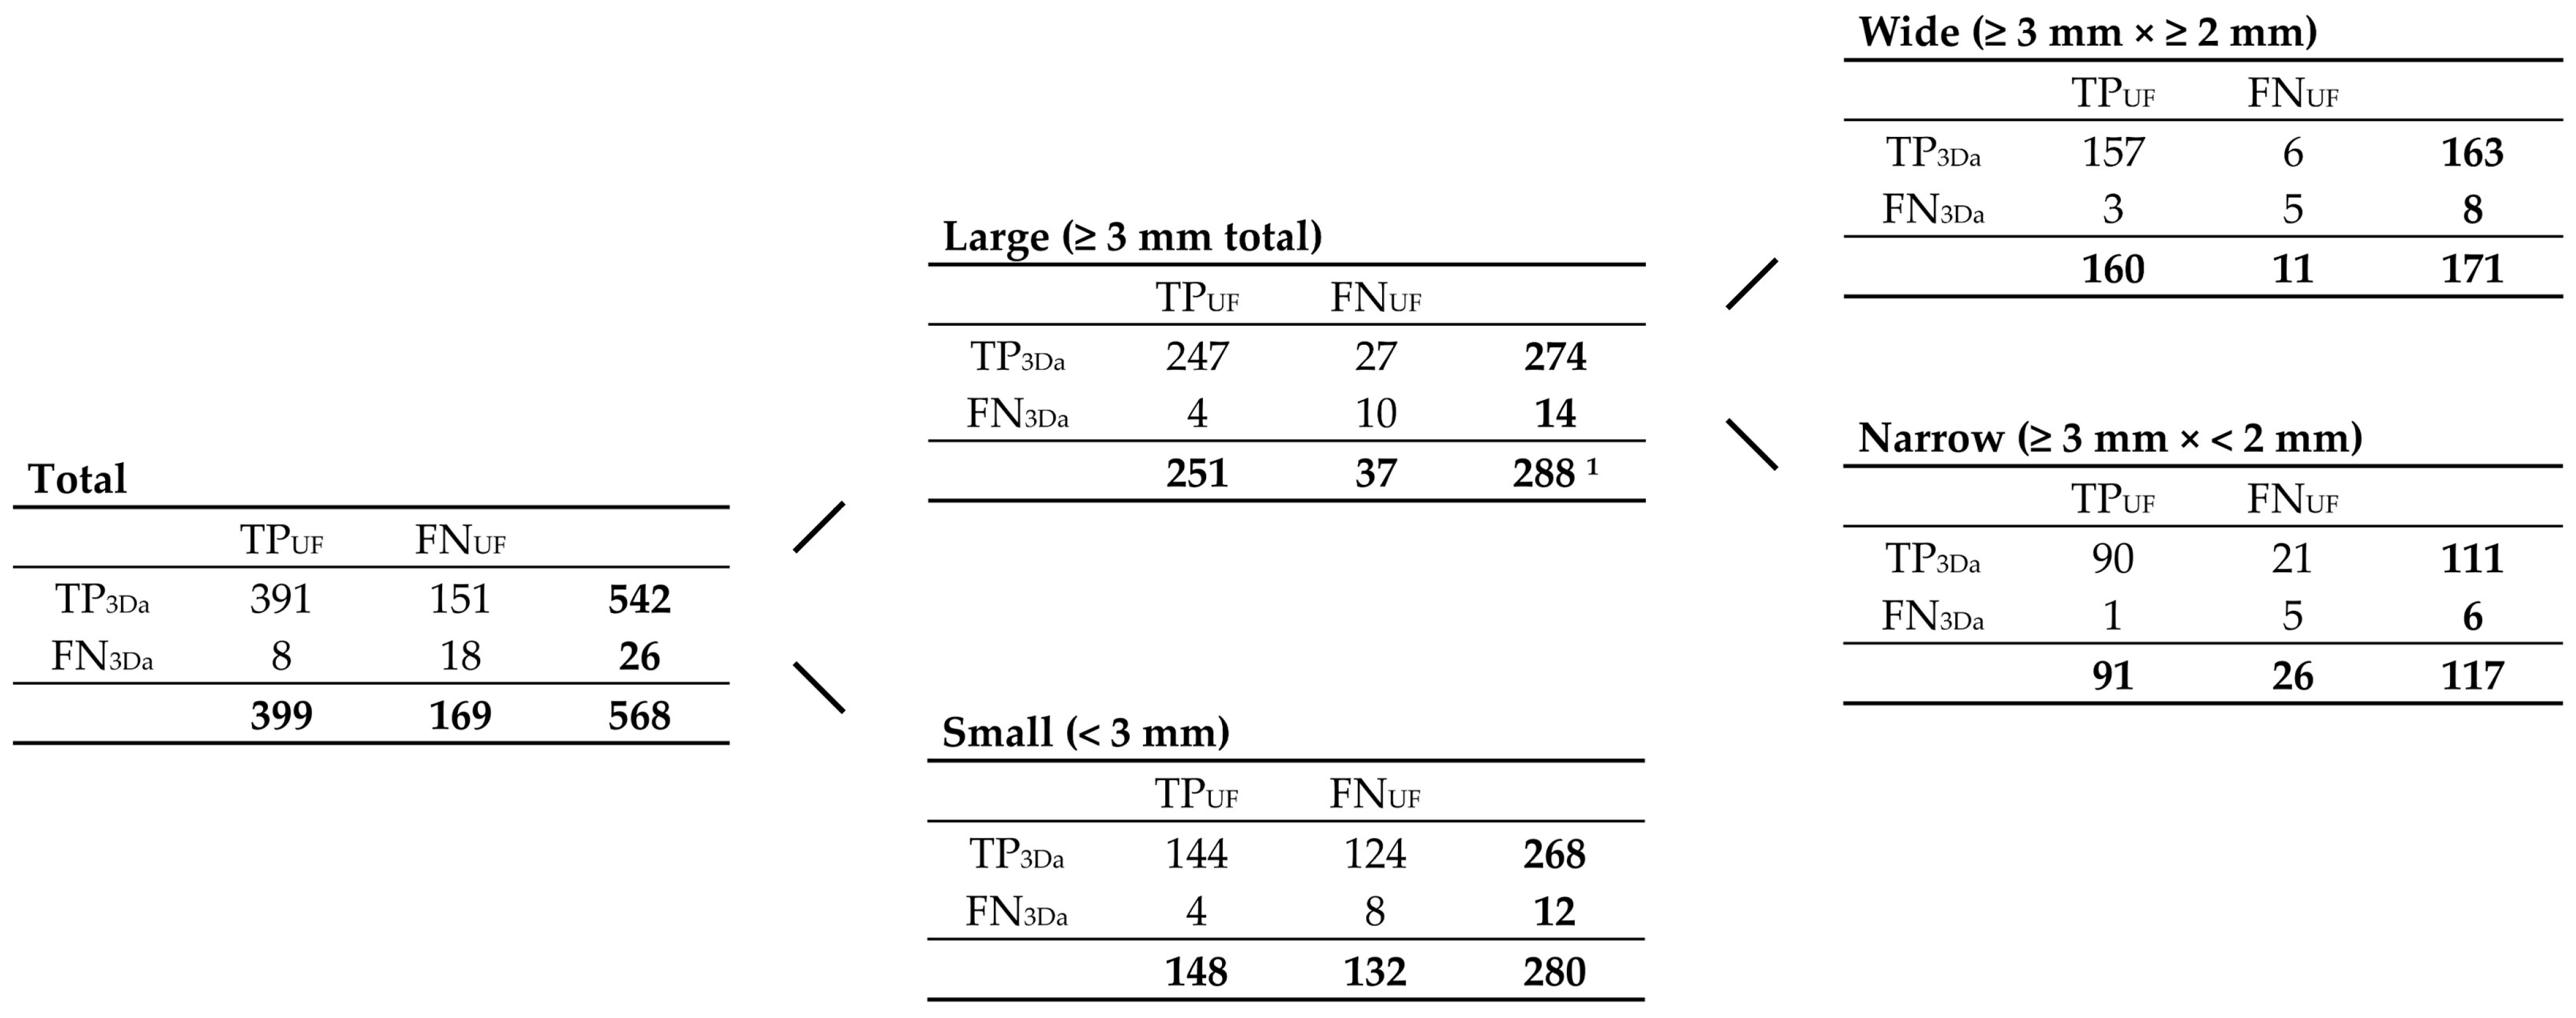

3.2.1. FLAIRUF Compared with FLAIR3Da

3.2.3. Dependence on Size and Location within FLAIRUF